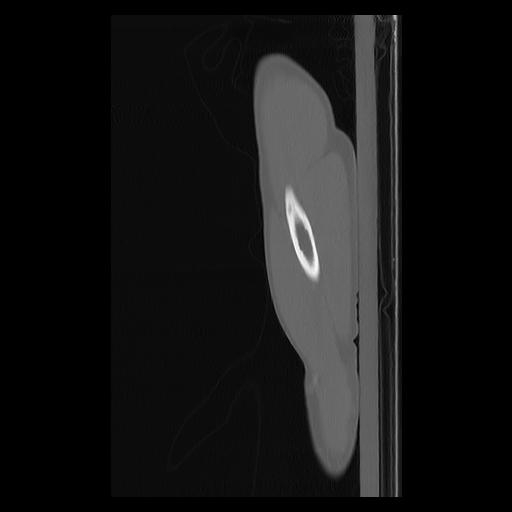

33 PULMON,CE,Sagittal,3.000,PULMON,Sagittal,